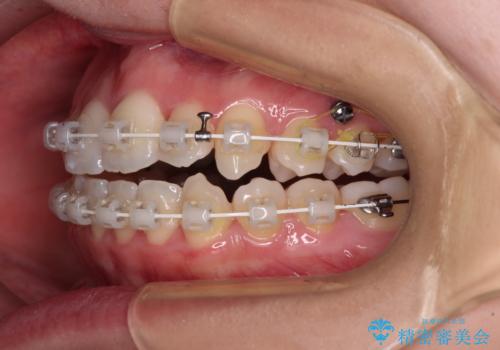

- 上下前歯のデコボコを気にして来院された患者様です。

上顎骨の横幅が狭く、奥歯は上顎よりも下顎が外側にある咬合状態でした。

歯列矯正では基本的に骨格を改善することはできませんが、急速拡大装置(MARPE)を使用することで上顎骨を側方に拡大させることができ、咬合状態を大きく改善することができます。

事前に急速拡大装置で側方拡大を行い、上下を目立たないワイヤー装置により歯列を整えていくこととしました。

急速拡大装置により骨格はある程度改善されましたが、奥歯の咬み合わせ改善に非常に時間がかかってしまいました。